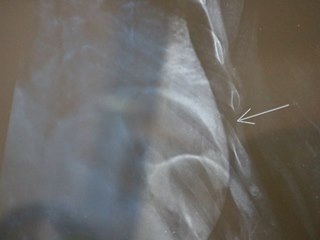

Gari cai em calçada quebrada e fratura costela no centro de Domingos MartinsEla deu entrada no hospital por volta das 5 horas da manhã, onde tomou um medicamento e foi liberada rapidamente. Ainda sentindo fortes dores, ela saiu do hospital e decidiu ir para o posto de saúde do município, pois as fortes dores ainda lhe incomodavam. Foi então que, lá chegando recebeu atendimento e uma solicitação de um raio x de urgência, pois as dores permaneciam com forte intensidade.

Desta forma, mais uma vez, sozinha e a pé, retornou ao Hospital de Domingos Martins para que fosse feito o raio x. Com exame em mãos, ela retornou ao posto de saúde, onde o médico que lhe atendeu, a diagnosticou com uma fratura na costela. O médico prescreveu medicamentos, forneceu um atestado médico de 15 dias , pediu que ela fosse para casa e ficasse em absoluto repouso. Assista o depoimento emocionado da servidora: